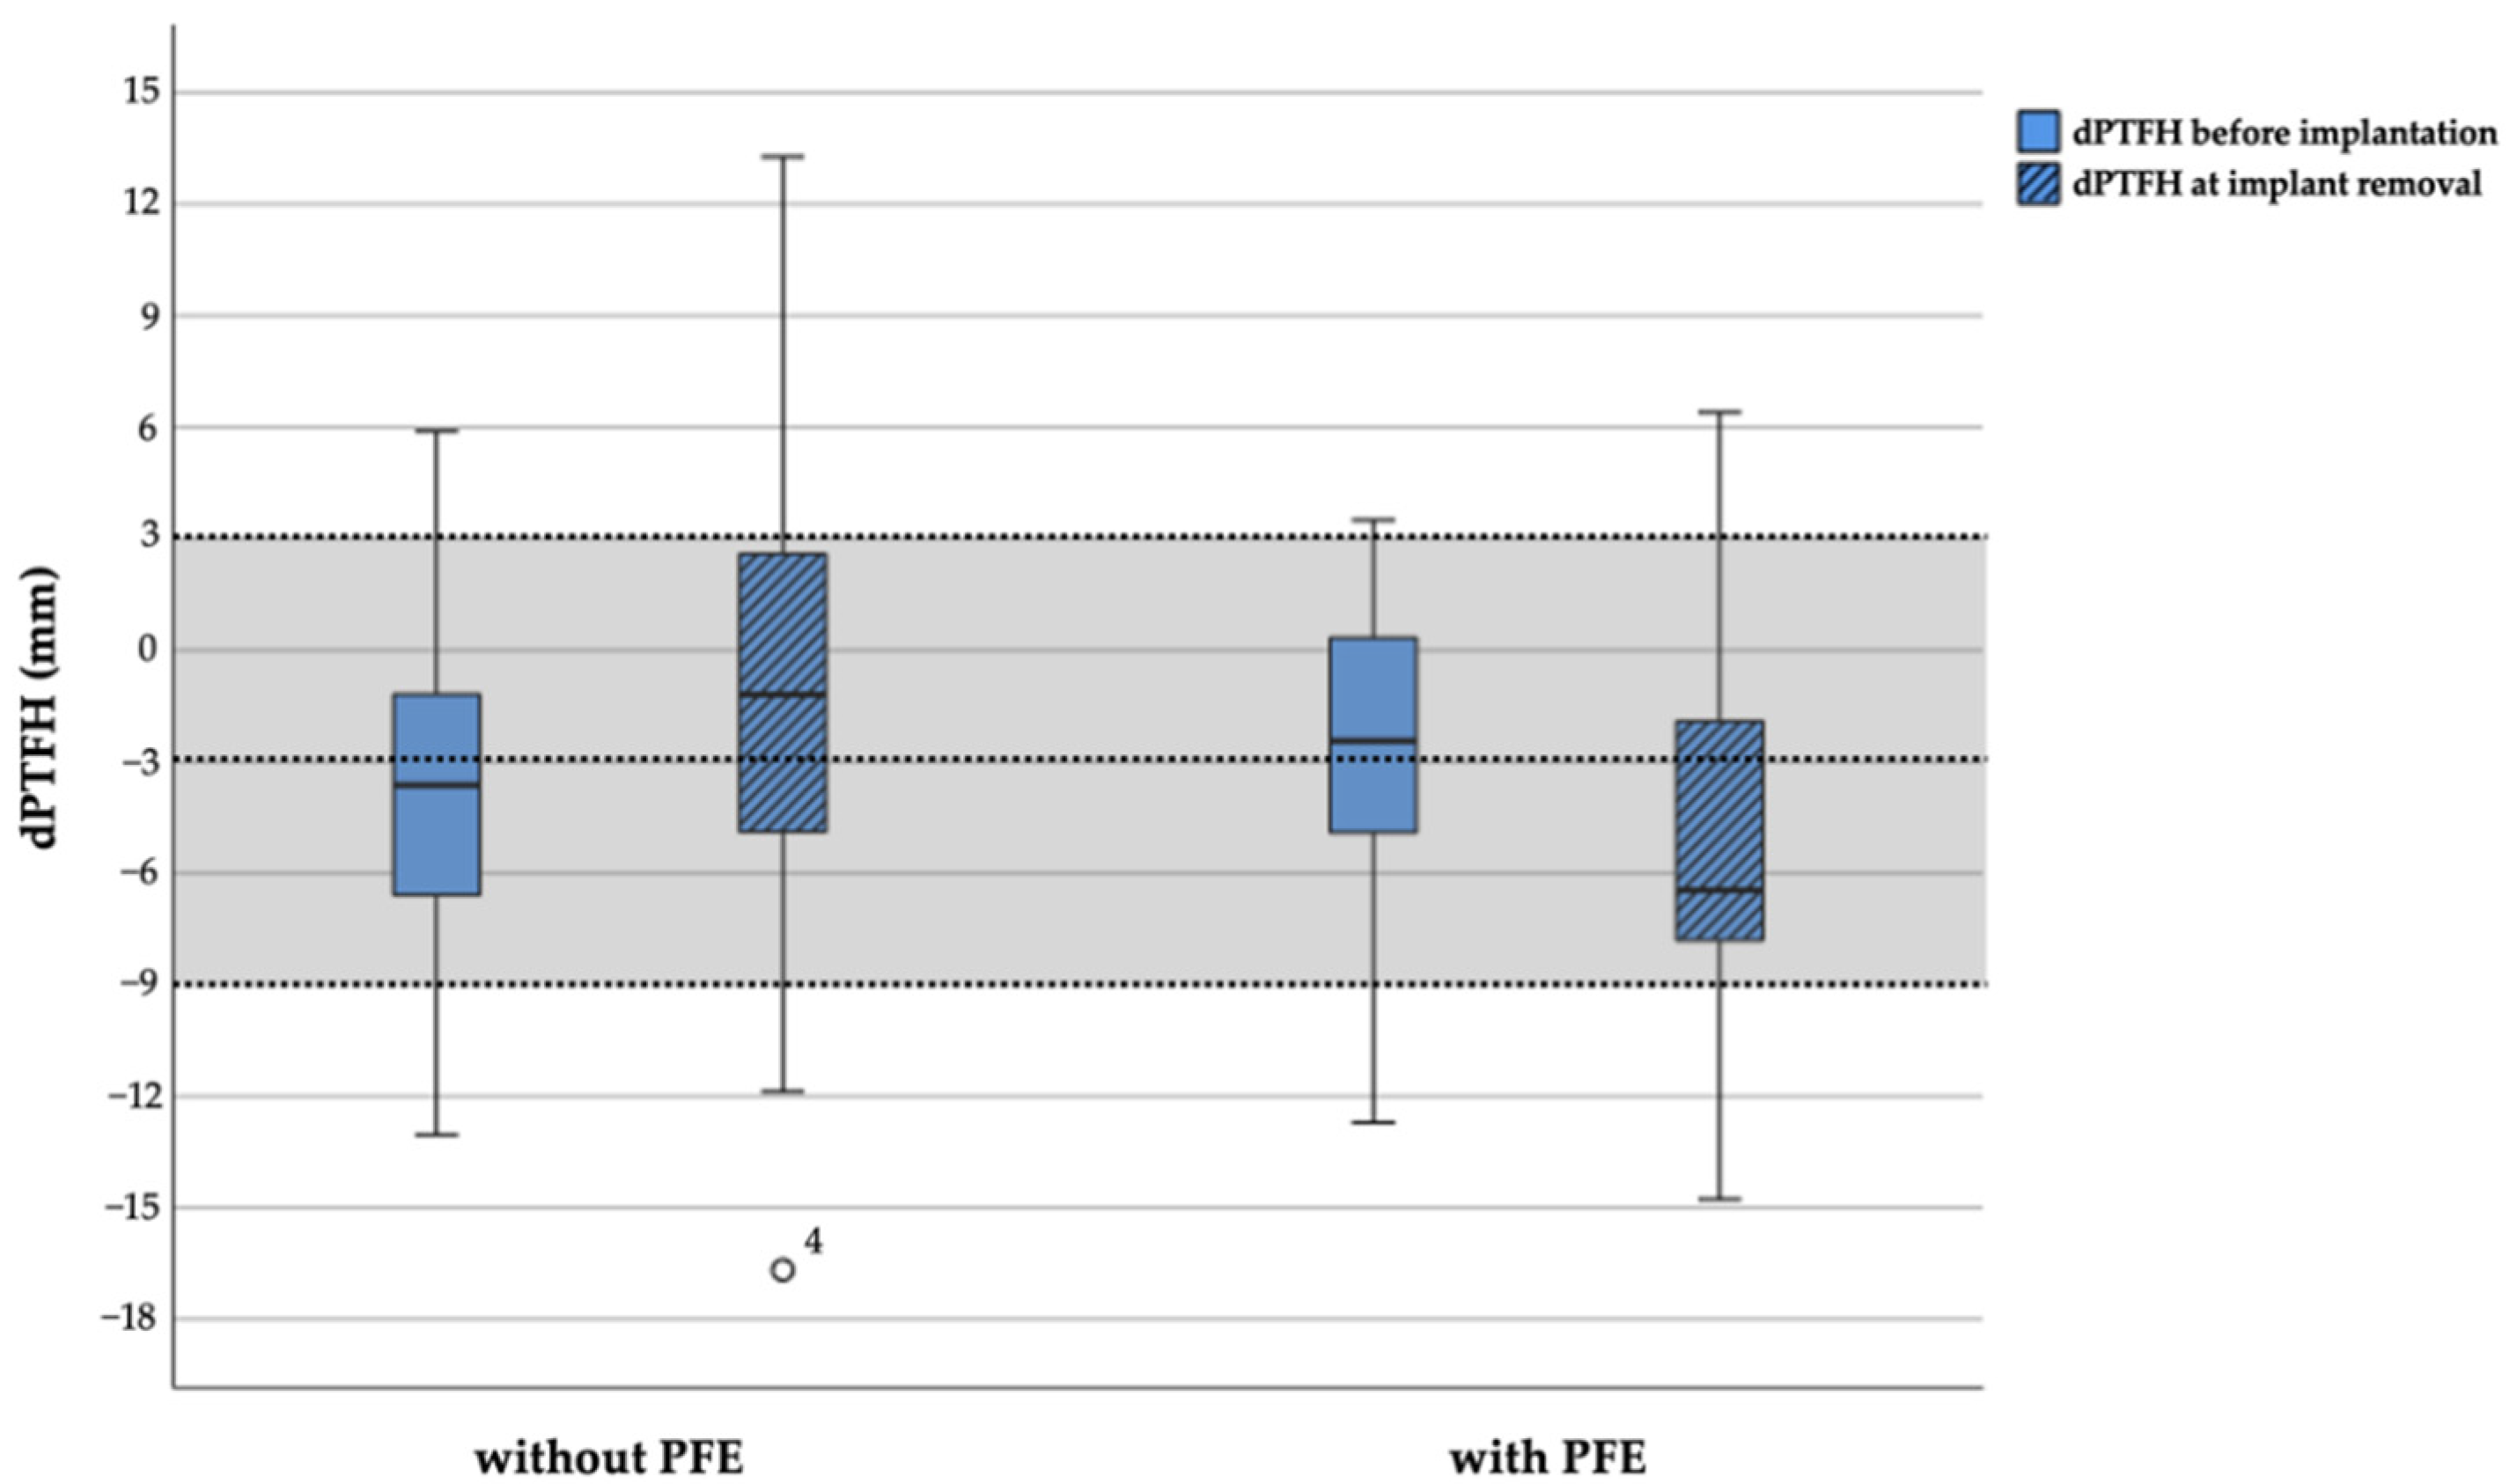

3.2. Radiographic Outcome Regarding Tibiofibular Relation

3.2.1. Comparison in Each of the Groups Treated with and without PFE

3.2.2. Comparison between the Groups Treated with and without PFE

| Distance proximal tibial physis to fibular head (mm; dPTFH) [16] | −3.4 (−12.7–3.5) | −5.1 (−14.8–6.4) | 0.223 | 3.7 (0.1–12) | −3.7 (−13.0–5.9) | −1.2 (−16.7–13.3) | 0.005 | 3.9 (0–15) | 0.876 |

| dPTFH within physiological range (%) | 21/27 (78) | 21/26 (81) | 1.000 | / | 25/31 (81) | 21/ 30 (70) | 0.508 | / | / |

| Distance proximal tibial physis to fibular head (dPTFH; mm) [16] | −3.4 (−12.7–3.5) | −3.7 (−13.0–5.9) | 0.546 | −5.1 (−14.8–6.4) | −1.2 (−16.7–13.3) | 0.018 |

| dPTFH within physiological range (%) | 77.8 | 80.6 | 1.000 | 80.8 | 70.0 | 0.508 |

| dPTFH (mm) | |||||||||

|---|---|---|---|---|---|---|---|---|---|

| Before Implantation | At Implant Removal | Change | |||||||

| RC | 95% CI | p-Value | RC | 95% CI | p-Value | RC | 95% CI | p-Value | |

| Intercept | −4.2 | (−5.7; −2.7) | <0.001 | −1.9 | (−4.1; 0.2) | 0.077 | 4.0 | (2.7; 5.3) | <0.001 |

| PFE (yes vs. no) | 1.4 | (−0.9; 3.7) | 0.234 | −2.5 | (−5.7; 0.8) | 0.142 | −0.4 | (−2.4; 1.6) | 0.677 |

| Predicted LLD (cm) centered at mean | −1.5 | (−2.8; −0.3) | 0.012 | −1.7 | (−3.5; −0.01) | 0.048 | 0.2 | (−0.8; 1.3) | 0.677 |

| Group Treated with PFE (n = 27) | Group Treated without PFE (n = 31) | |||||

|---|---|---|---|---|---|---|

| Before Implantation | At Implant Removal | p-Value | Before Implantation | At Implant Removal | p-Value | |

| dPTFH out of physiological range [16] | 6/27 (22%) | 5/26 (19%) | 1.000 | 6/31 (19%) | 9/30 (30%) | 0.508 |

| Proximal fibular overgrowth | 1/27 (4%) | 2/26 (8%) | 0.500 | 2/31 (6%) | 6/30 (20%) | 0.219 |

| Newly developed overgrowth | / | 2/26 (8%) | / | / | 5/30 (17%) | / |

| Proximal fibular shortening | 5/27 (19%) | 3/26 (12%) | 0.687 | 4/31 (13%) | 3/30 (10%) | 1.000 |

| Newly developed shortening | / | 2/26 (8%) | / | / | 1 (3%) | / |